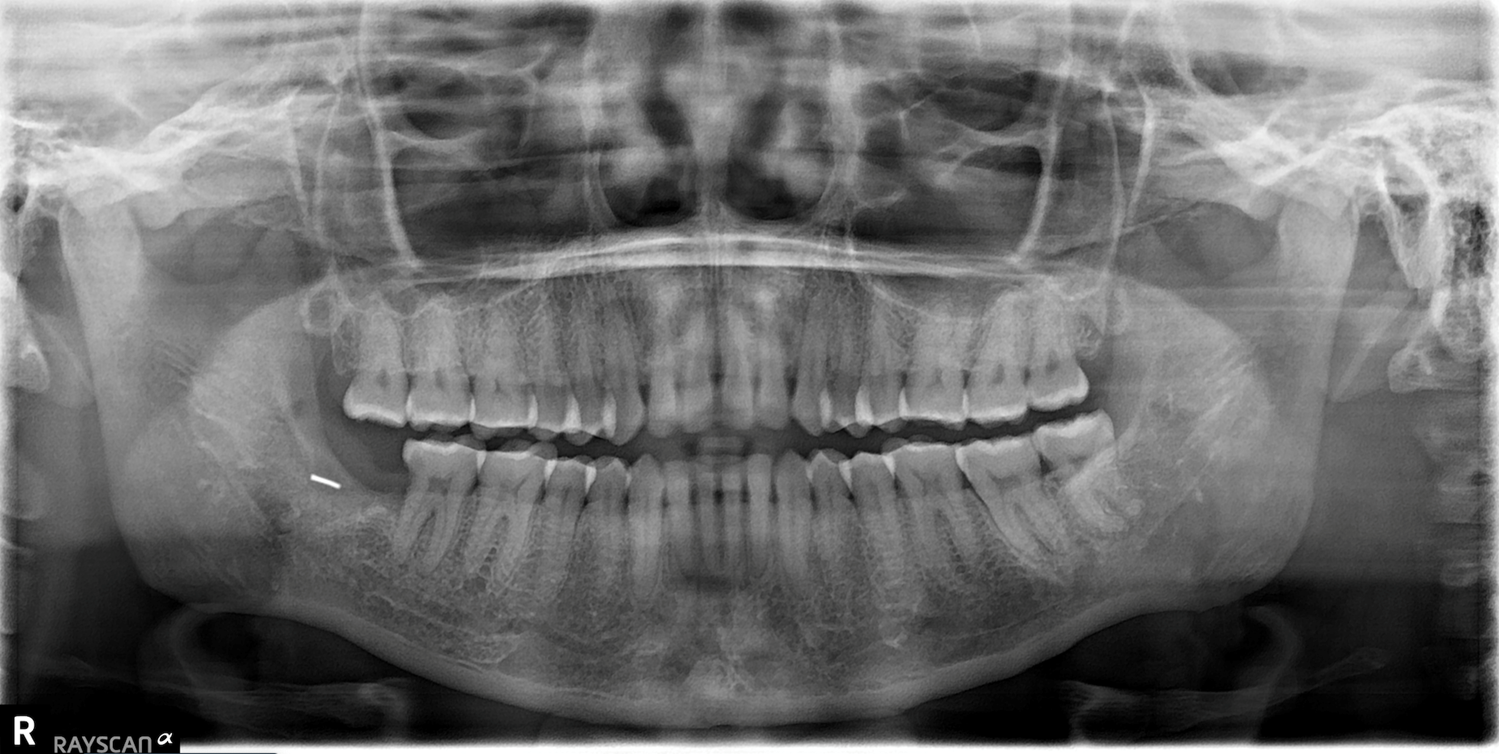

Foreign body in the mandible: a case report

Abdul Habib Mahomed Dadá, Gilberto Coelho Fernandes, Nelsa Maria José Sisto Inácio, Niucha Vasconcelos, Mahomed Sidique Abdul Cadar Dadá

35-39